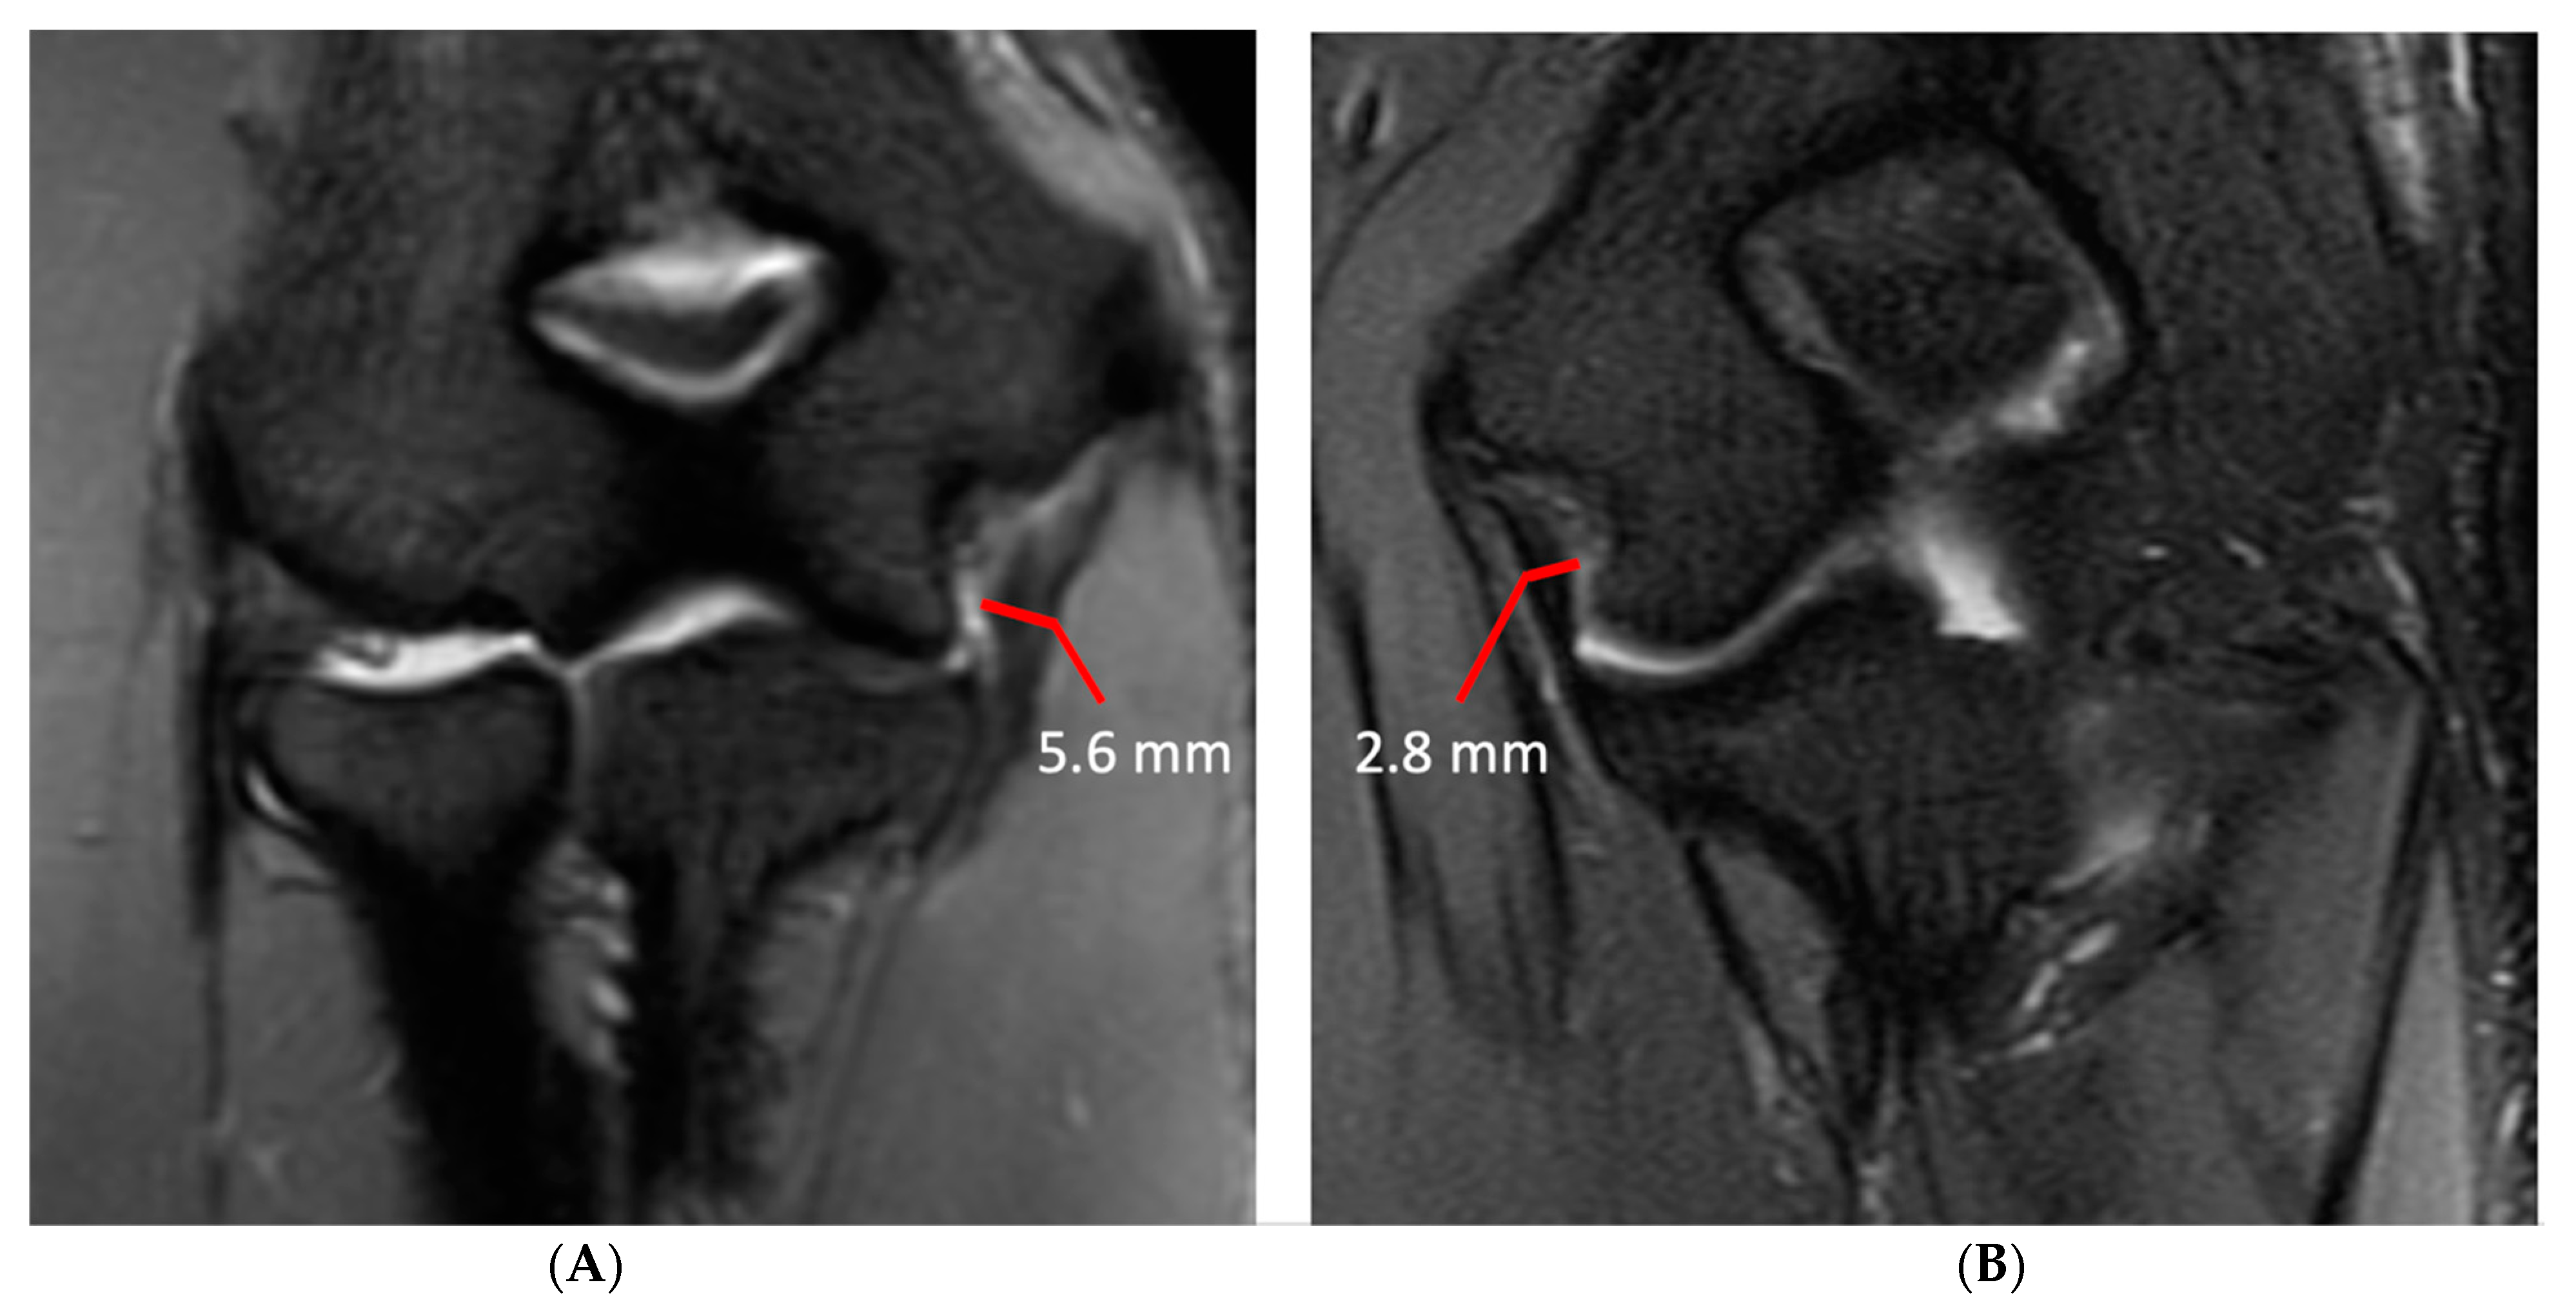

Injury of the UCL was scored as grade 1, 2 or 3. Injury was considered grade 1 if the ligament fibers were intact but there was periligamentous edema. If there was partial tearing of ligament fibers or abnormal signal within the UCL it was considered grade 2, and if fibers were completely disrupted it was considered grade 3. Ulnar collateral ligament (UCL) thickness and the maximal thickness of subchondral sclerosis in the central radial head, olecranon process, and posterior humeral trochlea were measured independently on separate workstations. UCL thickness was measured at the midpoint of the ligament on coronal fat-saturated T2-weighted or short-tau inversion recovery (STIR) images with a transverse measurement spanning the low signal ligament fibers and excluding any adjacent fat and fluid signal (Figure 1). The thickness of subchondral sclerosis in the radial head was measured on nonfat-saturated sagittal T1-weighted images, making the measurement perpendicular to the articular surface (Figure 2). On MR arthrograms the thickness of subchondral sclerosis in the radial head was measured on coronal non-fat-saturated T1-weighted images, as the only sagittal images acquired were fat-saturated. Subchondral sclerosis along the posterior humeral trochlea and olecranon process was measured on non-fat-saturated axial T1-weighted or proton-density-weighted images at the greatest anteroposterior length (Figure 2). No axial non-fat-saturated images were available in the MR arthrogram studies, but with appropriate windowing the subchondral sclerosis could still be readily identified on the fat-saturated images and was measured on the axial fat-saturated proton-density-weighted images.

Figure 1.

Ulnar collateral ligament measurement technique in two subjects. (A) Coronal STIR image of the right elbow in a right-hand-dominant 21-year-old male professional baseball player demonstrating an ulnar collateral ligament with a maximal transverse width of 5.6 mm. (B) Coronal T2 fat-saturated image of the left elbow of a 21-year-old left-hand-dominant male non-throwing control demonstrating an ulnar collateral ligament with a maximal transverse width of 2.8 mm.